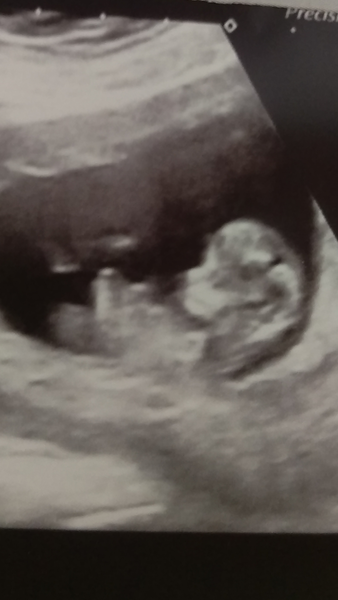

Here's mine, not the clearest pic, but saw it great on the screen. The white blob at the back of the neck is reflection from me taking a pic to put on here. Can't believe it's actually real! It was so amazing seeing it moving all over. Measurement was 1.7, so if bloods are all ok, should be fine, fingers crossed!! Date brought forward, it's now a bonfire night due date.